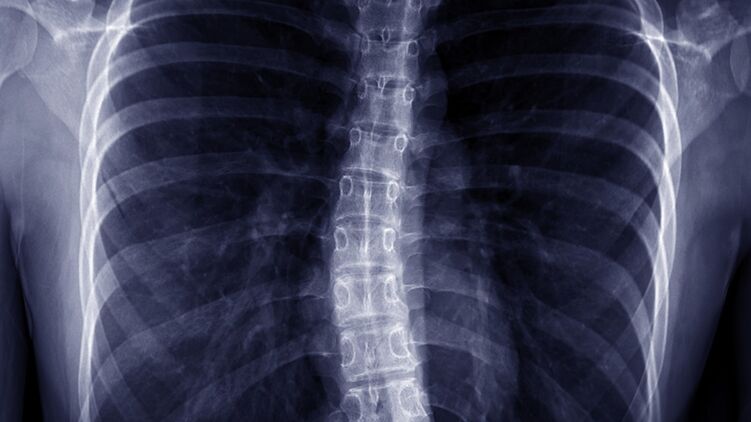

Сколиоз случается у всех: от младенцев до взрослых. Фото: facebook.com/moz.ukr

Этот недуг характеризуется S или C образным искривлением позвоночника в боковой плоскости. Человек может выглядеть так, будто он наклоняется в одну сторону. При этом могут поражаться как грудной, так и поясничный отдел позвоночника.

С увеличением искривление растет тенденция к ухудшению проблем общего состояния здоровья. Сильные сколиозы является причиной деформации туловища и его укорочения и приводят к уменьшению объема грудной клетки и брюшной полости.